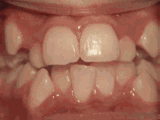

Deep overbite: Lower front teeth bite into palate

deep overbite

This adult patient (age twenty-five) required braces and jaw surgery to correct his severe overbite, with treatment taking two years. His problem could have been corrected without surgery if he had been treated before he was a teenager.